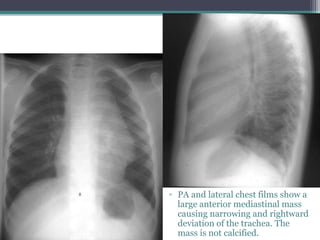

Eight year old male with a

โ–ซ PA and lateral chest films show a

large anterior mediastinal mass

causing narrowing and rightward

deviation of the trachea. The

mass is not calcified.

CT exam show a low

density mass in the

anterior mediastinum with

irregular walls with

calcium in it.

Dx Teratoma, Anterior

Mediastinal